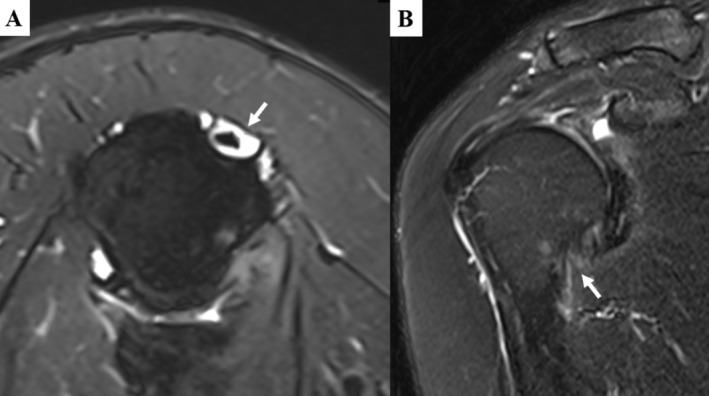

Objective: Idiopathic glenohumeral adhesive capsulitis, known as idiopathic frozen shoulder (IFS) and characterized by pain and limited motion of the shoulder, is often treated by arthroscopic capsule release surgery, though residual symptoms may remain postoperatively. Due to overlapping symptoms and shared anatomical involvement, it is hard to distinguish the source of shoulder pain between concurrent long head of the biceps tendon (LHBT) inflammation and IFS. The study aimed to verify that LHBT tenotomy, compared with leaving it in situ, could provide better pain reduction and shoulder mobility in early rehabilitation of post-arthroscopic IFS capsule release surgery.

Methods: From January 2020 to January 2022, 73 patients with idiopathic adhesive capsulitis were divided into two groups based on the preoperative LHBT lesions and treatment received for LHBT: tenotomy or left in situ. All patients underwent arthroscopic capsular release, coracohumeral ligament release, and subacromial decompression. Outcomes were measured before surgery and at 1, 3, 6, 12, and 24 months and final follow-up postoperatively, including shoulder functional scores, joint range of motion, visual analog scale (VAS) score for pain, and complications. T-test, Chi-square test, and Fisher's test were performed to analyze the data.